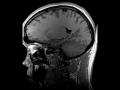

As per a recent study, neurological complications of COVID-19 can include delirium (abrupt change in the brain that causes mental confusion and emotional disruption), brain inflammation, stroke, and nerve damage. ...

Neurological complications of COVID-19 can include delirium (abrupt change in the brain that causes mental confusion and emotional disruption), brain inflammation, stroke and nerve damage, a new study has revealed. ...